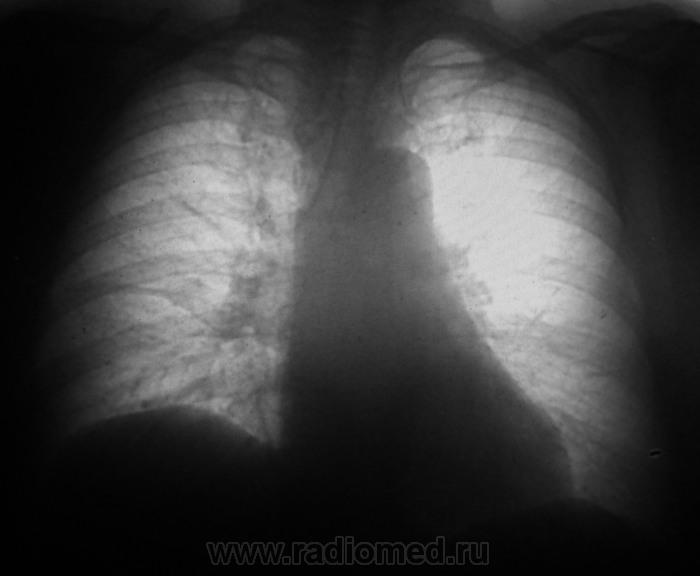

Через полтора года...

Мезотелиома!?

Пациент полтора года выращивал это ходил? По первым ФЛГ норму поставили?

Выросло,однако.